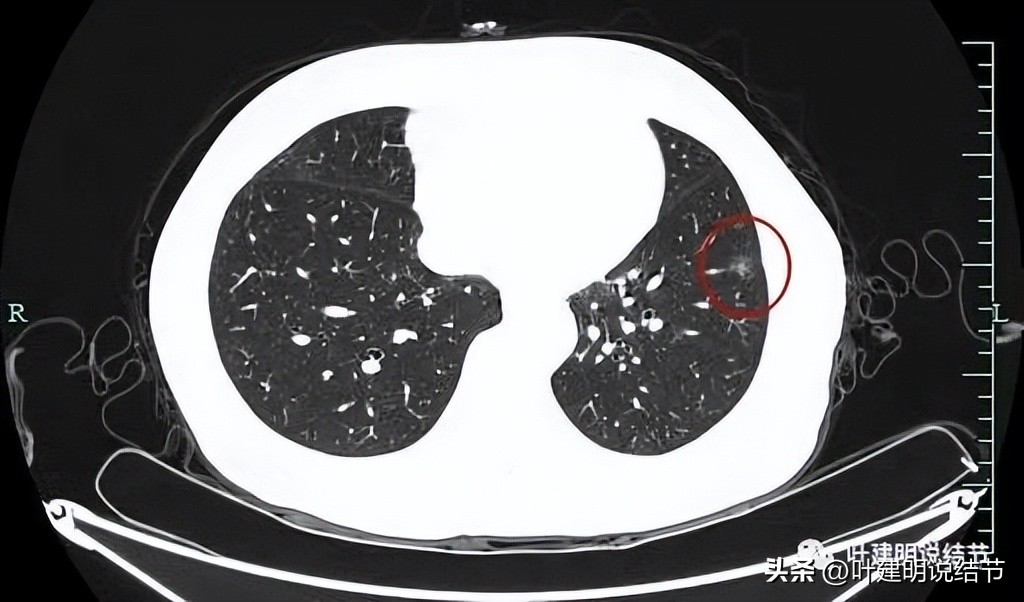

再看左下叶的主病灶,此层见其是磨玻璃密度,轮廓较清,内部密度欠均匀。

有明显血管征,血管进入后有分支发出,病灶表面显得有毛刺样。

病灶中间有空腔。

囊壁较薄,但不均匀,有的地方还是显略厚了点的。

似乎见微小血管走向病灶。

微小血管征确实有。